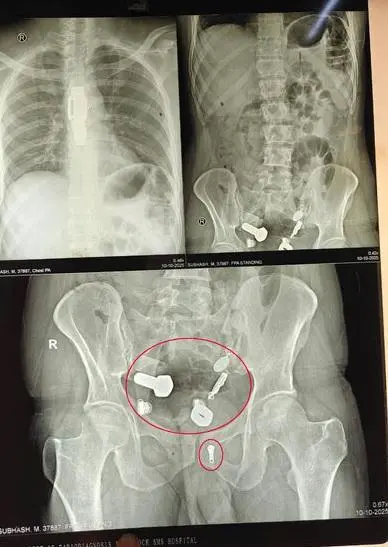

直到安排了影像學檢查,全體醫護人員才被螢幕上的畫面驚得說不出話:男子的食道中段卡著一整只手錶,而腸道裡更是像被刻意塞滿了「五金配件」,鐵片、螺絲、螺帽與大理石塊隨處可見,簡直是個移動的小型雜物堆。

印度齋浦爾一名34歲男子因劇烈腹痛嘔吐就醫,竟發現食道卡著整只手錶,腸道堆滿鐵片等硬物。醫護團隊歷3小時手術取出異物,研判其行為與精神疾病引發的幻覺及衝動有關,術後心理治療至關重要。(來源:網絡)